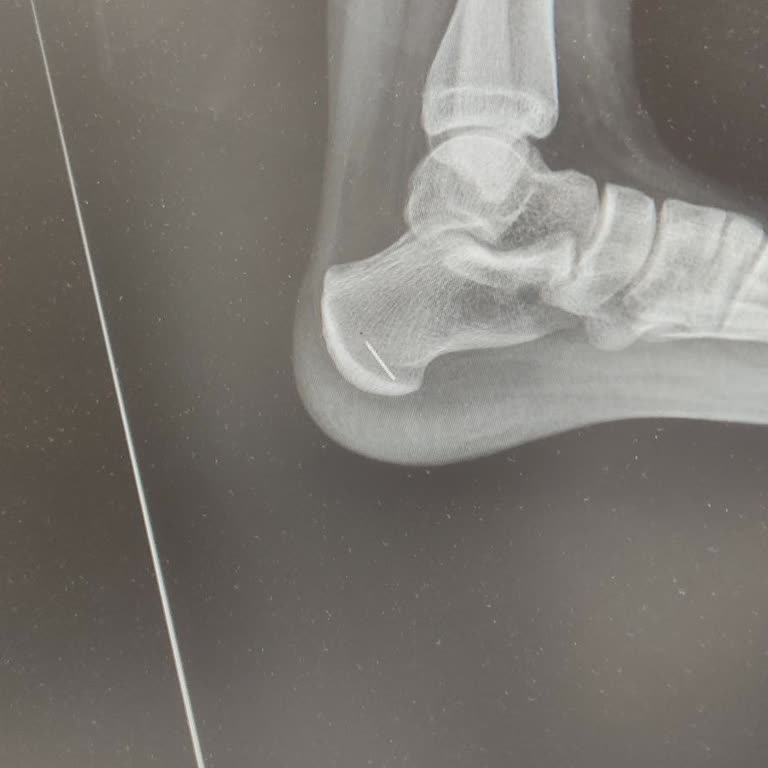

Hasta T. C. Kimlik numarası... Olan kızım... 26 Ekim 2025 gecesi evde, halının üzerinde gözden kaçan bir dikiş iğnesine yanlışlıkla bastı. Olayın hemen ardından Bayrampaşa Kolan Hastanesi acil servisine başvurduk. Acil serviste görevli doktor, sadece elle iki kez dokunarak muayene etti, herhangi bir...